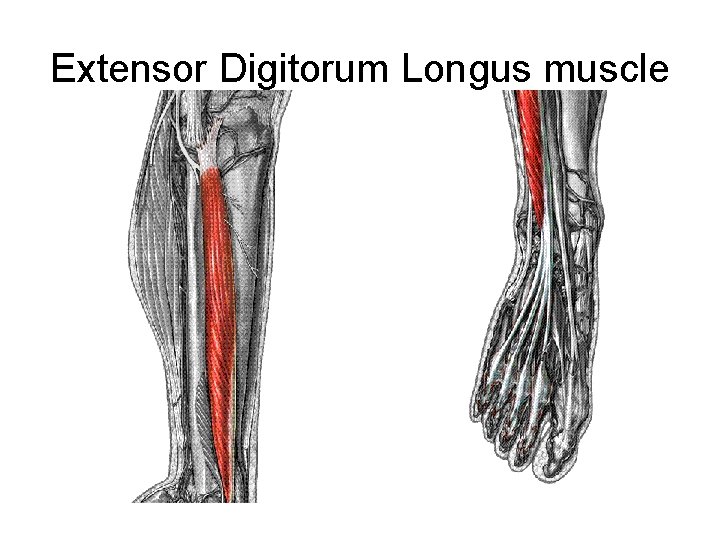

Extensor Digitorum Longus muscle

• L 5, S 1 • Extends lateral four toes • Ankle dorsiflexion • Everts the foot at the subtalar joints